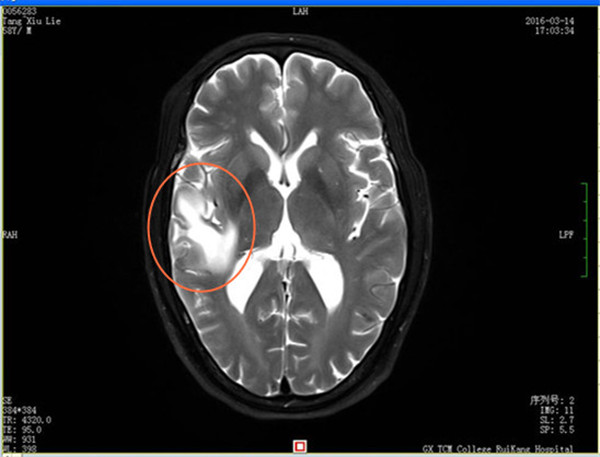

今年58岁唐先生,因多年前误食“米猪肉”,在四年前被确诊为“脑囊虫病”、“症状性癫痫”。行驱虫、抗癫痫治疗后病情好转,之后癫痫没有再发。但在2016年3月初,在无明显诱因的情况下,唐先生出现头晕,伴四肢乏力,为求进一步诊治来到瑞康医院脑病科住院治疗。经检查,在唐先生的MRI增强检查中发现颅内有炎性亮点,进一步血清检查证实为脑囊虫病,经针对病情治疗后得到控制,病灶逐渐消失,症状也得到了明显的改善。

治疗前